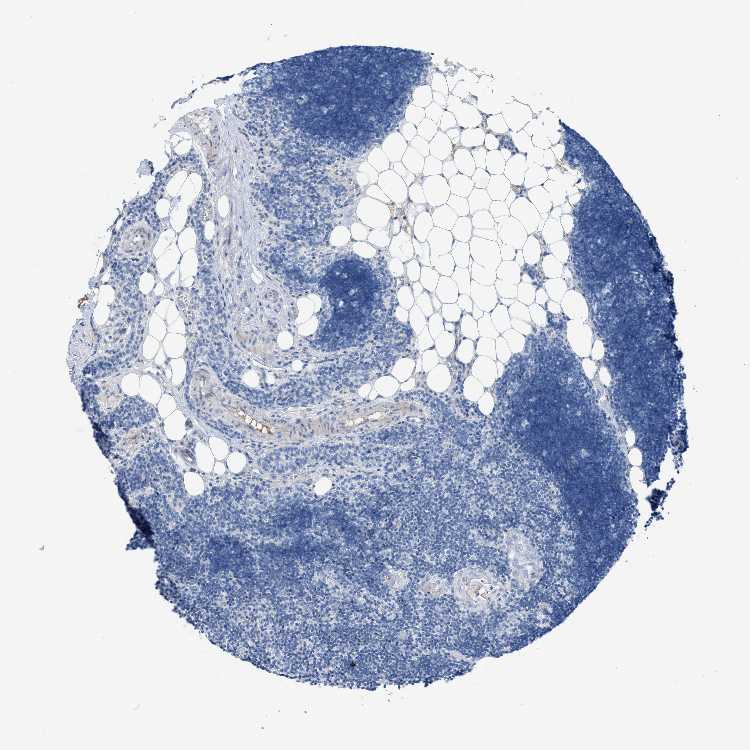

TISSUE PRIMARY DATA LYMPH NODE Show tissue menu

Lymph node

Lymphoid tissue

LYMPH NODE - Expression summary

LYMPH NODE - Antibody stainingi

Antibody staining in the annotated cell types in the current human tissue is reported as not detected, low, medium, or high, based on conventional immunohistochemistry profiling in selected tissues. This score is based on the combination of the staining intensity and fraction of stained cells.

Each image is clickable and will lead to virtual microscopy that enables deeper exploration of all samples and also displays staining intensity scores, fraction scores and subcellular localization as well as patient and tissue information for each sample.

Antibody HPA021818Antibody HPA024742

Germinal center cells Not detectedNot detected

Non-germinal center cells Not detectedNot detected